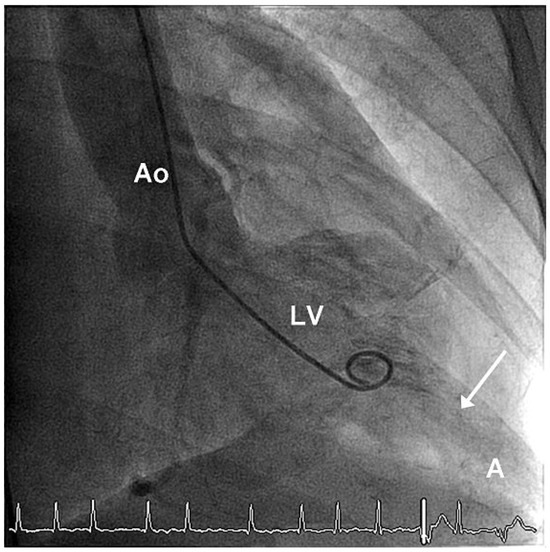

Giant Apical Aneurysm without Coronary Artery Disease

by Stéphane Chevallier and Jean-Christophe Stauffer

A 66-year-old patient with some years’ history of apical hypertrophic cardiomyopathy treated by beta-blockers attended for follow-up echocardiography [...] Full article